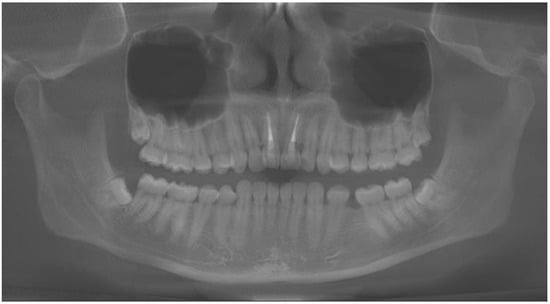

3.1. Case No. 1

3.2. Case No. 2